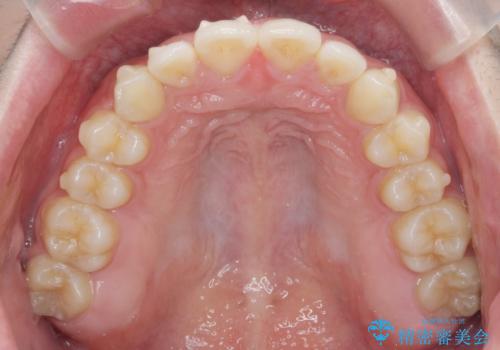

- 出っ歯のように見える前歯の角度を治したい、と矯正治療を希望され来院されました。

抜歯をせずにマウスピース矯正システムインビザラインを用いてしっかりと前歯の角度を改善していきます。

前歯の角度だけでなく内側に倒れ込んでいた奥歯もしっかり起こすことで咬合関係も理想的に仕上げています。